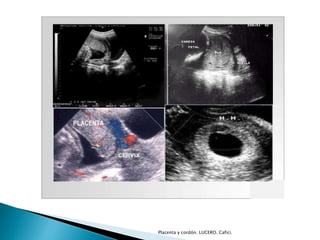

 Ecográficamente se observa un anillo

hiperecogénico alrededor del saco

gestacional.

Placenta y cordón. LUCERO. Cafici.

 Reconocida por ultrasonido a las:

◦ 9 o 10 semana

◦ Engrosamiento del halo hiperecogénico que rodea

el saco gestacional.

 Flujo intervelloso a partir de:

◦ 13 semanas

◦ Doppler color